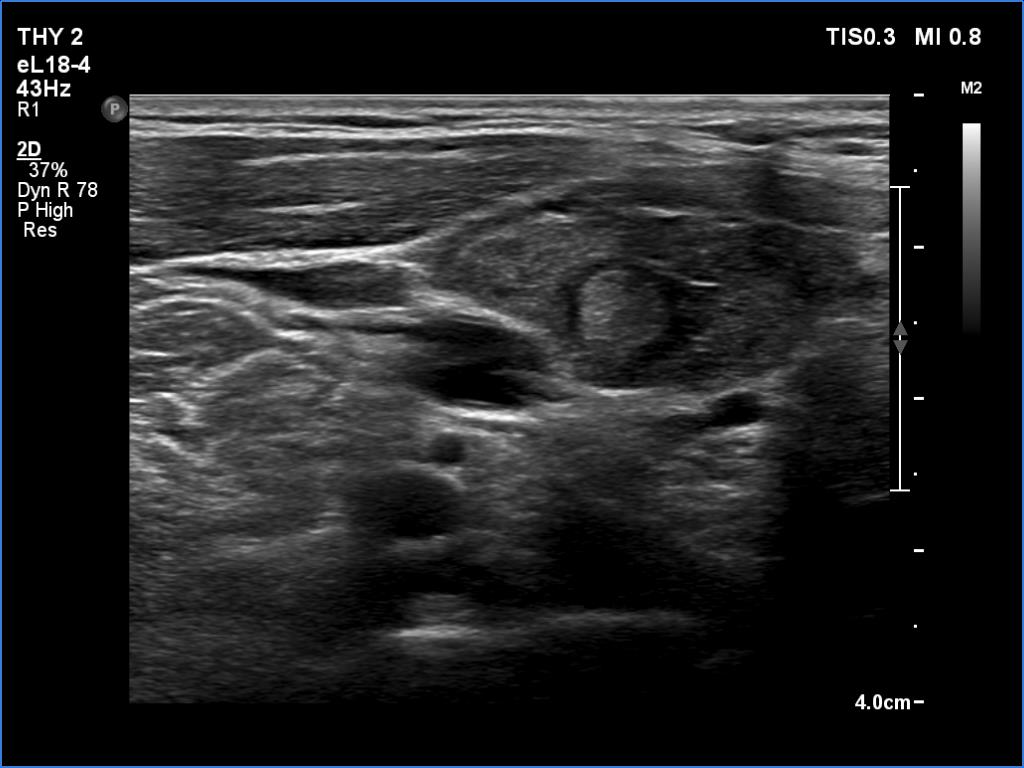

Graves' disease - case 799

Follow-up investigation 5 weeks after the first visit (ultrasonographic picture 2)

Upper part of the right lobe, longitudinal scan.